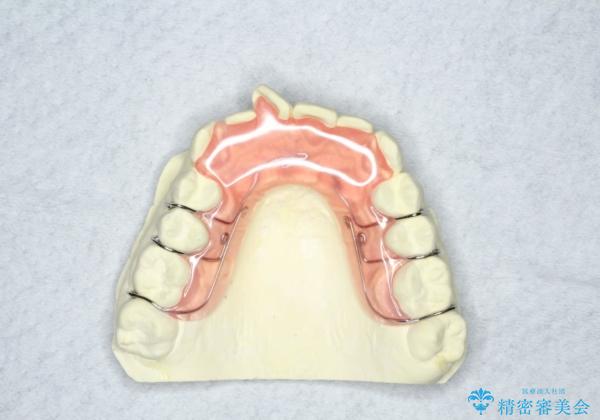

ハーフリンガル ワイヤー矯正による非抜歯・過蓋咬合の治療

- 審美装置

- 非抜歯、大臼歯遠心移動による臼歯関係の是正・過蓋の改善をハーフリンガル・ワイヤー矯正にて計画した。